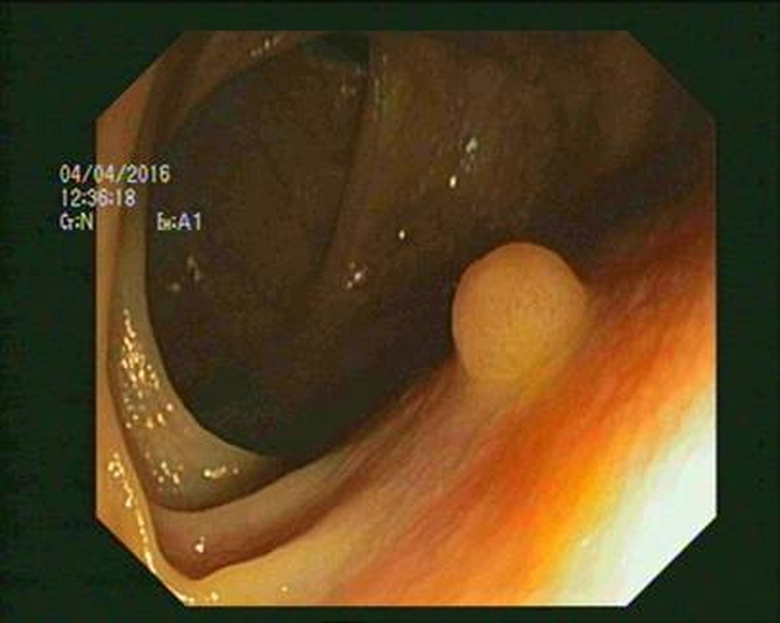

Theo ThS.BS Nguyễn Ngọc Khánh – Quyền Trưởng Khoa Ngoại Vinmec Times City: “Phần lớn ung thư đại trực tràng đều bắt nguồn từ các polyp. Thông thường sau 5-10 năm một polyp đại tràng – trực tràng có thể bị ác tính hóa và tiến triển thành ung thư.

Vì thế chương trình tầm soát ung thư hàng năm của Hiệp hội Ung thư Mỹ khuyến cáo: Ngoài 30 tuổi kể cả nam và nữ, đặc biệt là những người trong gia đình có tiền sử ung thư đại trực tràng, cứ 5 năm nên nội soi đại tràng/ lần. Trong nội soi phát hiện polyp đại tràng thì cần cắt bỏ để phòng ngừa ung thư”.

![]() |

Trong nội soi phát hiện polyp đại tràng, bác sĩ sẽ cắt bỏ để phòng ngừa ung thư |